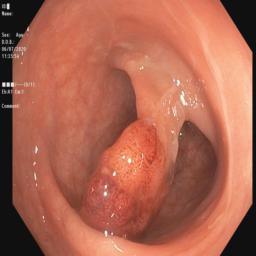

Table I presents our extensive experiments on the polyp segmentation results under FedAvg and FedProx frameworks and benchmarking results with other algorithms. For the metrics defined above, we have highlighted the best-obtained results in bold. Fig. 4 shows samples of the polyp segmentation results. Our comprehensive evaluations reveal that thresholding-based FDG methods (either soft or hard-thresholding) perform better than others.